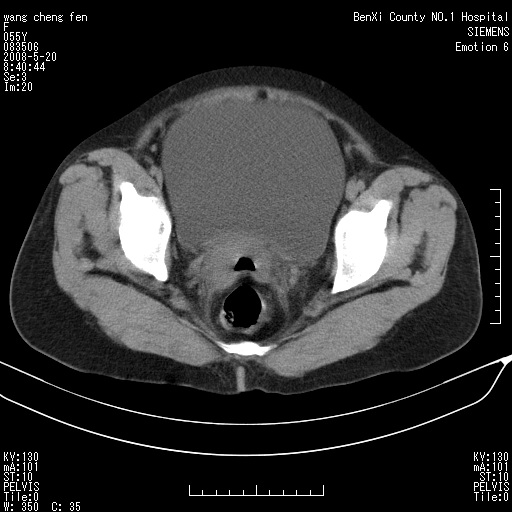

女、绝经后阴道流血3个月

左侧附件区可见一囊性占位,边缘清楚,内可见不规则形软组织影 ce:囊壁及内部可见强化 考虑 卵巢囊腺瘤

左侧附件区巨大囊实性病灶,边缘光整,病灶囊壁较厚,增强示囊壁及实性部分明显强化,强化呈度与宫体实质大致相同,宫腔积液征像,未见盆腔积液等其他异常,考虑左侧卵巢囊腺癌,不除外囊腺瘤及浆膜下肌瘤坏死

左侧附件区巨大囊实性病灶,边缘光整,病灶囊壁较厚,增强示囊壁及实性部分明显强化,强化呈度与宫体实质大致相同,宫腔积液征像,未见盆腔积液等其他异常。绝经后阴道流血3个月,结合病史左侧卵巢囊腺癌首先考虑,宫腔扩大不除外累及。期待结果。

支持浆膜下子宫肌瘤.之前由于网络原因未看全图片,现在重看,宫颈见一类圆形低密度影,增强轻度强化,低于肌层强化,宫腔扩大,考虑宫颈癌伴宫腔积液可能性大.